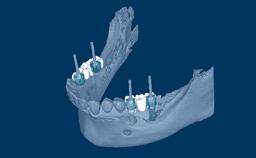

Papel dos Implantes na Odontologia

A perda dentária é uma das incapacidades mais comuns que afetam a humanidade, e é uma consequência de doenças dentárias, tumores da região orofacial e trauma. A perda dentária também pode ocorrer devido à agenesia. A extensão dos espaços edêntulos pode variar, desde espaços únicos na região anterior das mandíbulas ou em segmentos posteriores, espaços edêntulos extensos e edentulismo total. Isso pode resultar em prejuízo funcional, estético e fonético para o indivíduo em questão. A ausência de elementos dentários tem um enorme impacto no bem-estar psicossocial desses indivíduos e, como tal, os dentistas têm um papel importante em ajudar esses indivíduos a melhorar a qualidade de suas vidas.

- identificar indicações específicas onde os implantes podem ser usados para substituir dentes ausentes

- reconhecer as indicações do conceito de planejamento protético reverso e prévio para o uso de implantes dentários